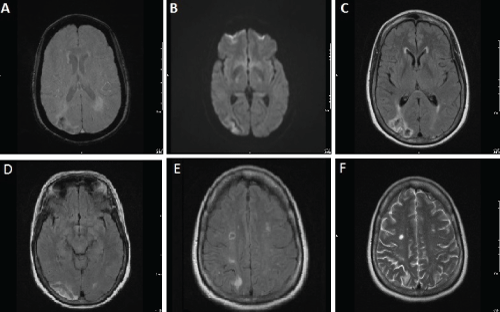

As no clear causes for the recurrent strokes were currently identified, and initial cardiac work-up was negative at the other institutions, we elected to conduct a TEE. The TEE revealed a trileaflet aortic valve with mildly calcified aortic cusps and a 10 mm long thin fibrin strand on the aortic valve prolapsing into the left ventricle outflow tract in diastole, strongly suggestive of Lambl's excrescences, based on echocardiographic criteria (Figure 2). No other valvular, atrial or ventricular abnormalities were identified. There were no thrombi and absent intracardiac shunts. A moderate (2-4 mm) atheroma was seen in the ascending aorta.

Figure 2: Transesophageal echocardiogram view of giant Lambl's

excrescences deriving from the aortic valve (A- valve is closed; B- valve is

opened)